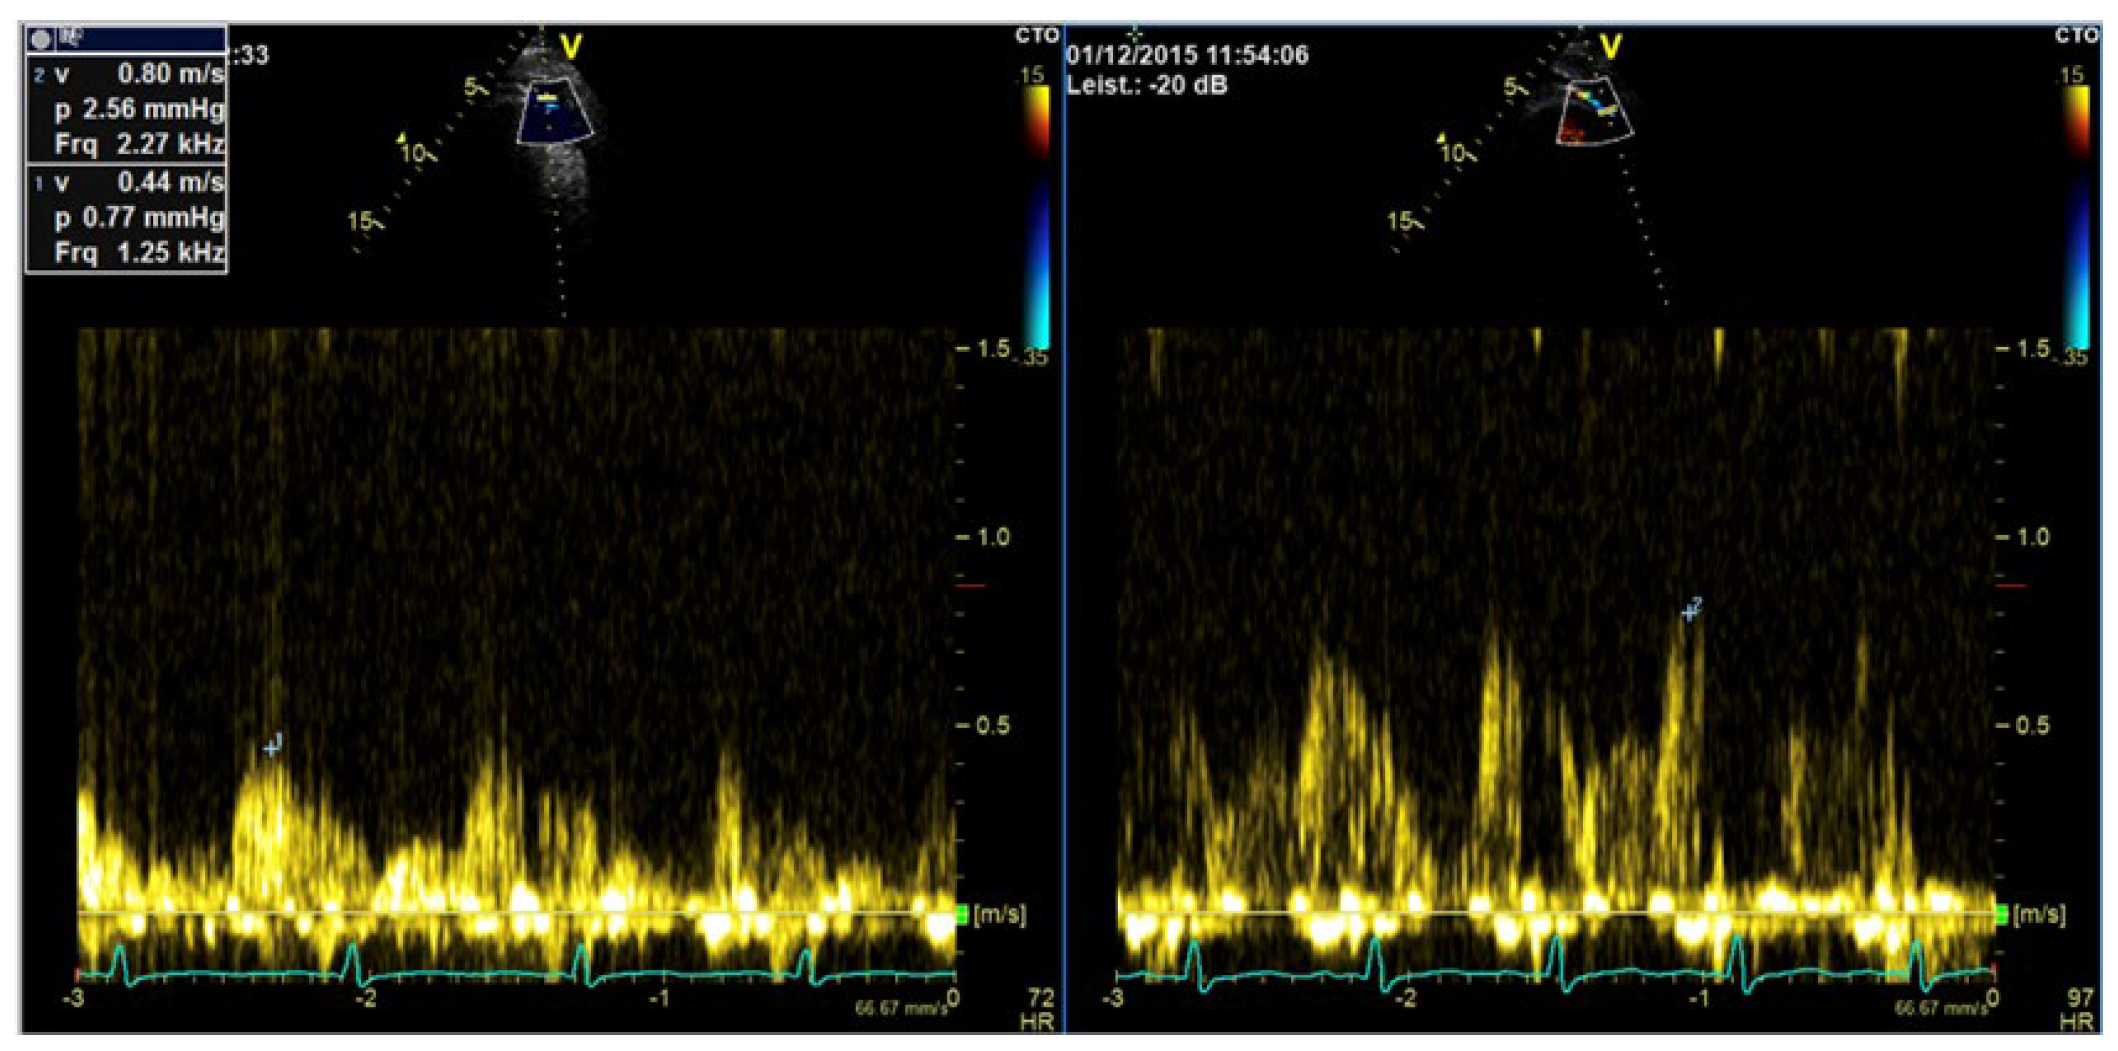

6. Enhancement of Doppler Signals

6.1. Background and Indications

6.2. How to Measure LAD Coronary Flow Velocity

6.3. Preparation and Performance for Enhancement of Valvular Flows

Technical Aspects, Settings

6.4. Velocity Measurements on Enhanced Doppler Recordings

| Imaging method | CW Doppler for aortic stenosis/tricuspid regurgitation PW-Doppler: for pulmonary–venous flow |

| Imaging planes | Same as for non-contrast Doppler imaging, the enhanced color Doppler signals facilitate the alignment of the cursor for spectral Doppler measurements |

| Contrast application | Bolus injection, the recordings can be performed during the washout after recordings for assessment of LV function |

| Typical findings | Intensive Doppler spectra Consider reduction in gain or power. |